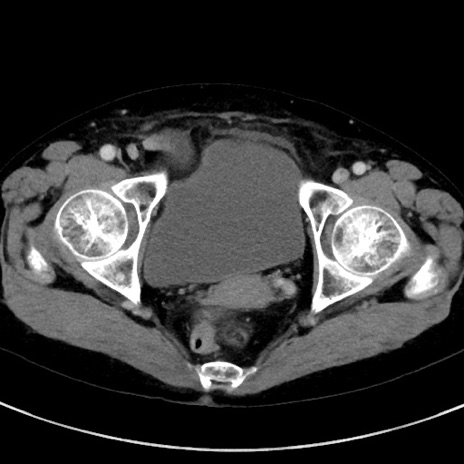

症例23(横断像)

【症例】70歳代女性

【主訴】下腹部痛・嘔吐

【現病歴】2日前より腹痛あり。昨日嘔吐あり。症状改善しないため来院。

【既往歴】胃GISTに対して胃部分切除後。

【身体所見】BT 37.1℃、BP 128/77mmHg、腹部:平坦・軟、下腹部に圧痛あり。

【データ】WBC 10200、CRP 0.31